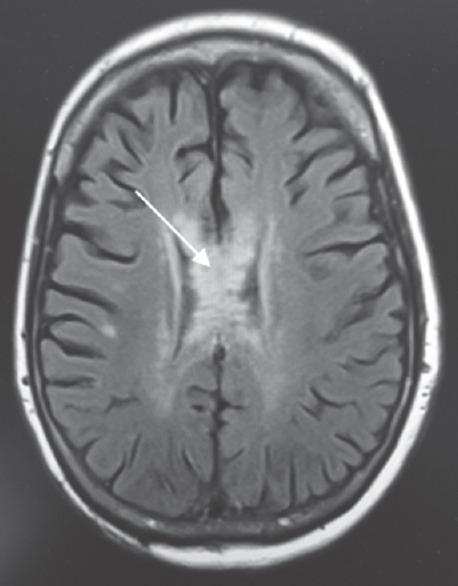

Idiopathic normal pressure hydrocephalus (INPH) is characterized by the clinical triad of gait and cognitive dysfunction and urinary incontinence. Ventriculoperitoneal (VP) shunting is often required for treatment. Review of literature shows few case reports discussing benign magnetic resonance imaging (MRI) T2 hyperintense changes in the corpus callosum of NPH patients after shunting due to mechanical compression of the middle and posterior regions of the body against falx cerebri leading to ischemic demyelination. These changes can be a delayed phenomenon and may interfere with clinical evaluation and may lead to unnecessary procedures and investigations. We present a patient with NPH who was admitted to the neurocritical care unit in coma with quetiapine and trazodone overdose. Diffuse changes in the body of the corpus callosum were seen on MRI suspicious for acute vasogenic edema due to drug overdose. However, it was later determined to be due to the VP shunting for the NPH. We report this case to raise the awareness of neuroimaging changes in patients with NPH who have VP shunting.